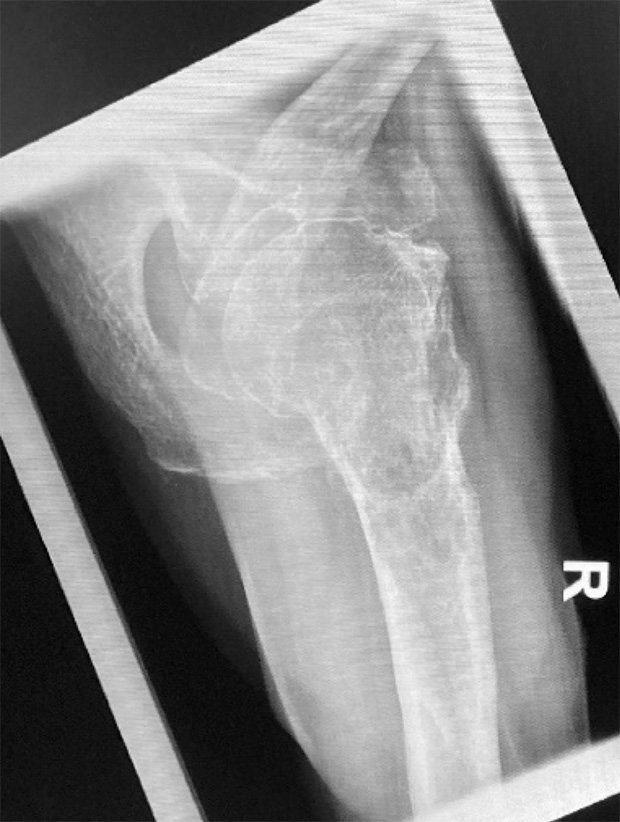

Pre-op

Picture 3 and 4: X-ray m-l and MRI

Patient:

- 73 year old male with bone tumor in the proximal humerus right side